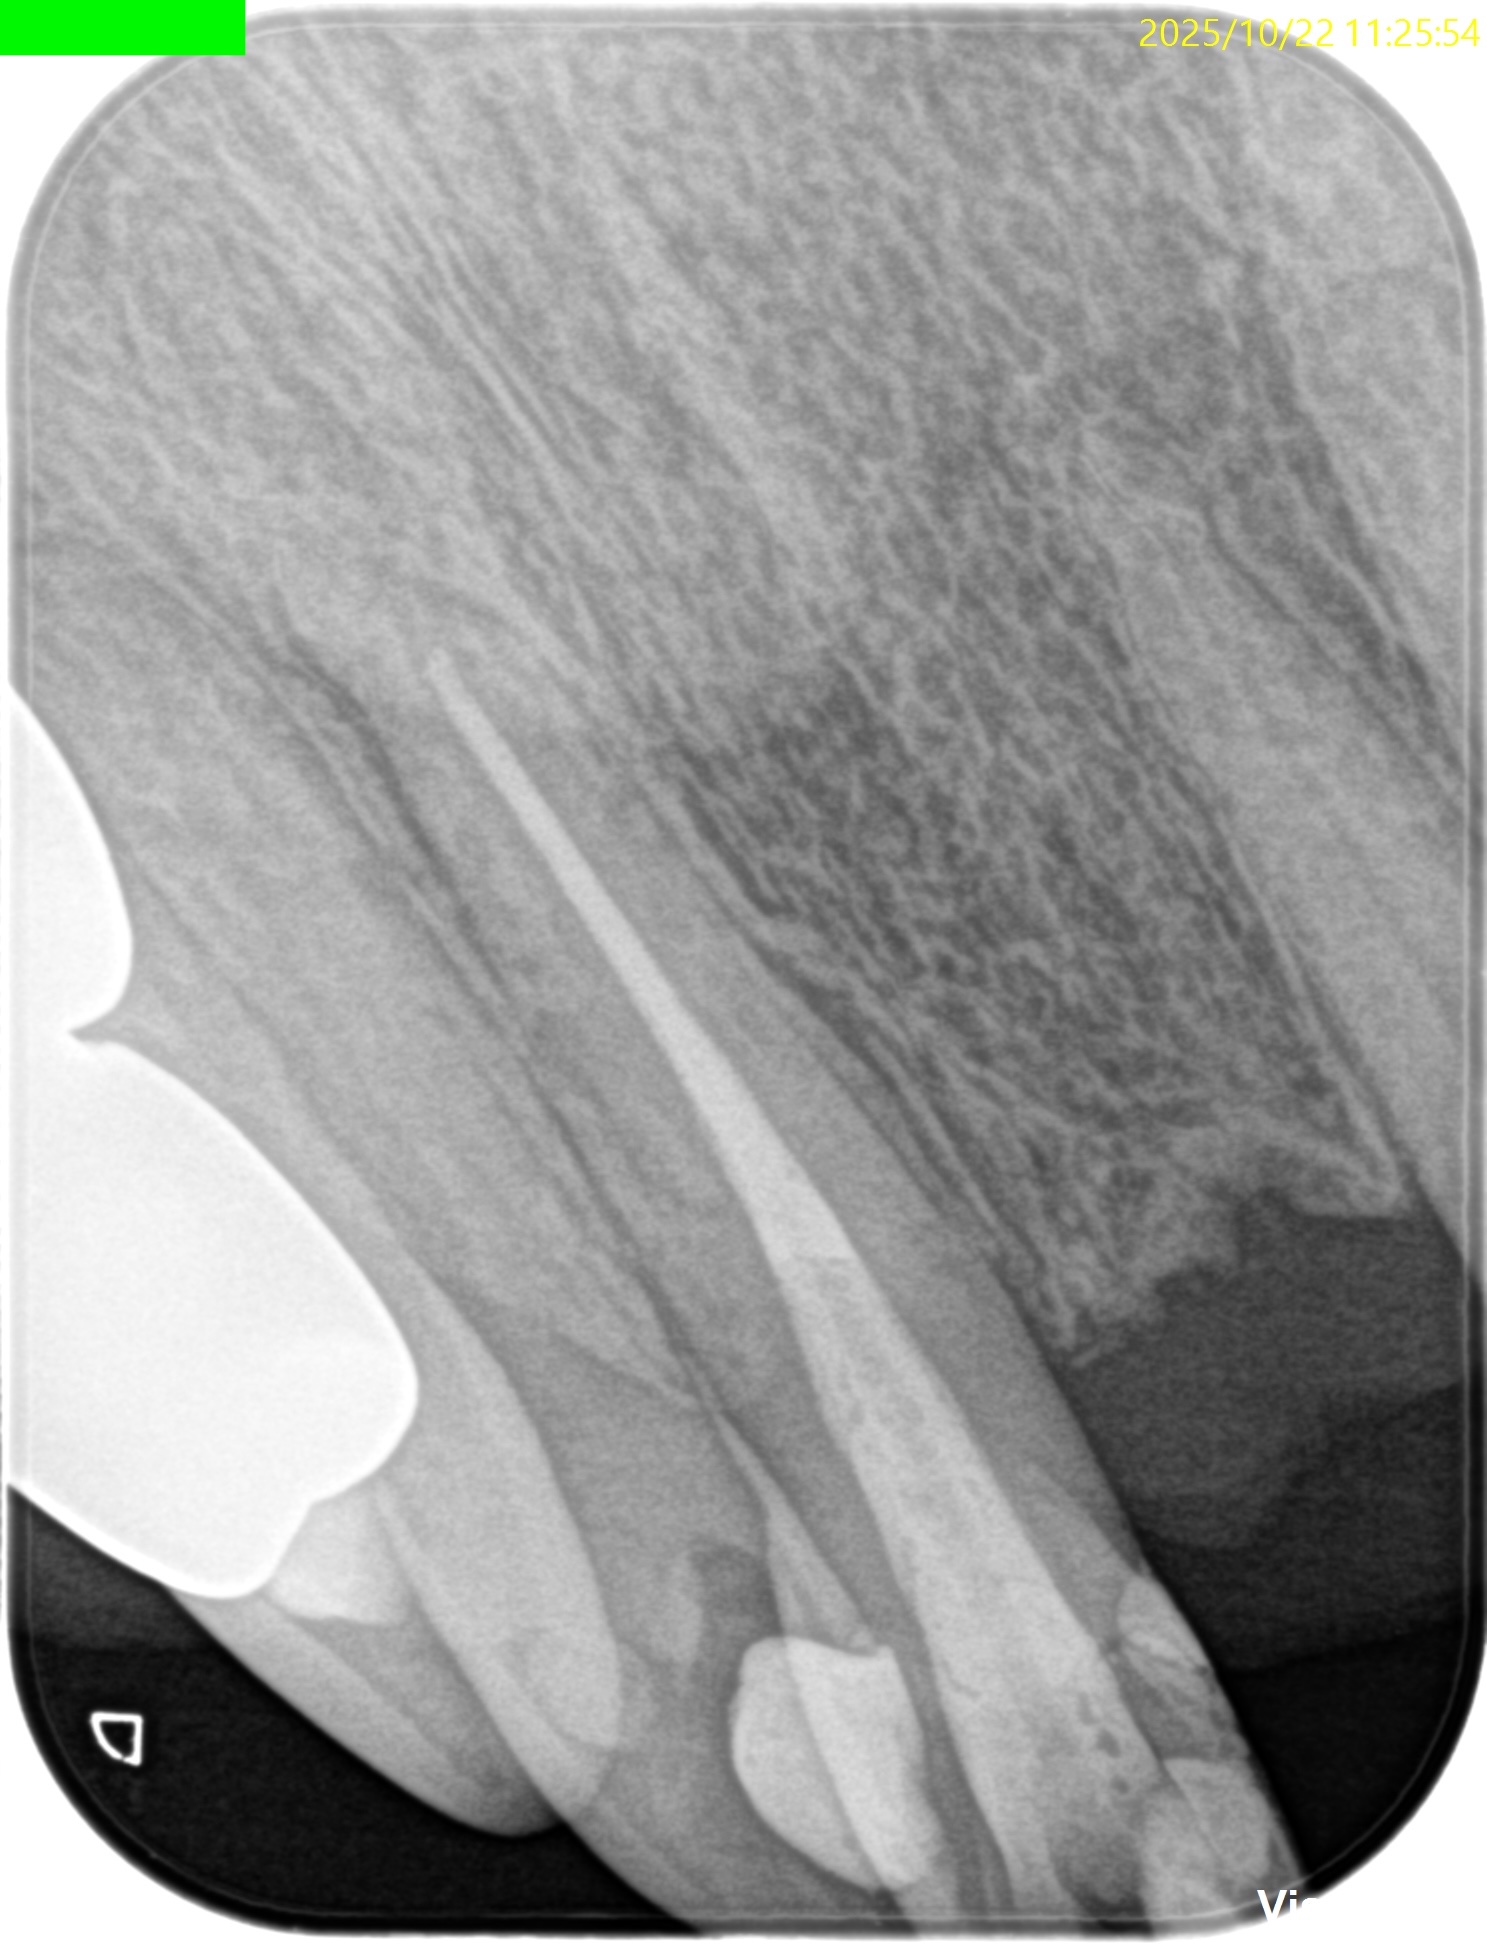

PA(2025.10.22)

歯内療法学的診断(2025.10.22)

Pulp Dx: Previously treated

Periapical Dx: Symptomatic apical periodontitis

Recommended Tx: Re-RCT+Core build up with Fiber Post